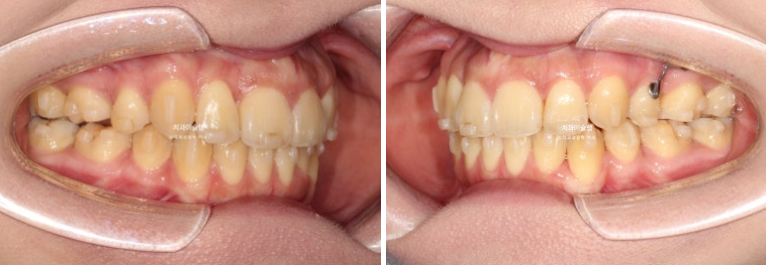

23.10

23년 10월 교정치료를 이해 온 30대 환자분입니다.

약 2mm 정도의 중심선 불일치 그리고 덧니가 보입니다.

개방교합도 있고

30년간 공간이 없어서 미처 내려오지 못한 작은어금니도 있습니다.

덧니가 워낙 심해 작은어금니 4개 발치가 불가피한 상황입니다.

초진 안모에서는 약간의 입술돌출이 보입니다.

그러나 턱끝이 도드라진 편이라 입이 많이 들어가지 않게 치료해야며 뚱한 느낌 정도만 개선하는 것이 좋습니다,

인비절라인 치료 선택하셨습니다.